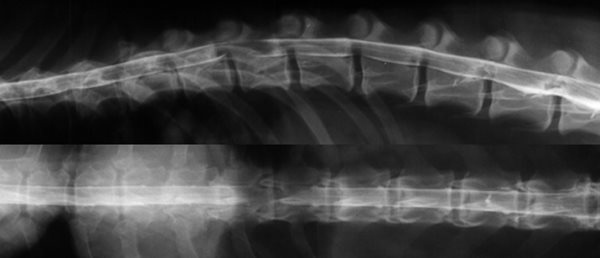

La myélographie.

C'était l'examen de choix jusqu'à ces dernières années pour le diagnostic des hernies discales, le développement du scanner tend actuellement à le supplanter.

Il s'agit d'un examen radiologique sous anesthésie. Un produit de contraste iodé radio-opaque est injecté dans l'espace sous arachnoïdien. Des clichés sont alors effectués pour mettre en évidence des déviations de la moelle épinière ou des modifications de la prise du liquide de contraste.

Myélographie Hernie Discale T12-T13

La myélographie est souvent suffisante pour établir un diagnostic et poser l'indication chirurgicale, cependant dans certains cas, en présence d'un gros oedème médullaire ou de difficultés de latéralisation, il peut être nécessaire d'avoir recours à des moyens d'imagerie tridimensionnels comme le scanner ou l'IRM.

Les imprécisions liées au caractère bidimensionnel de l'examen le rend actuellement obsolète face à la tomodensitométrie numérisée. Son usage peut encore se justifier en situation d'urgence neurologique chirurgicale et en l'absence de disponibilité d'un scanner. La myélographie, avec ses carences, demeure un examen utile, tant par sa simplicité de réalisation que par sa grande accessibilité matérielle (un simple appareil de radiologie permet d'y avoir recours).